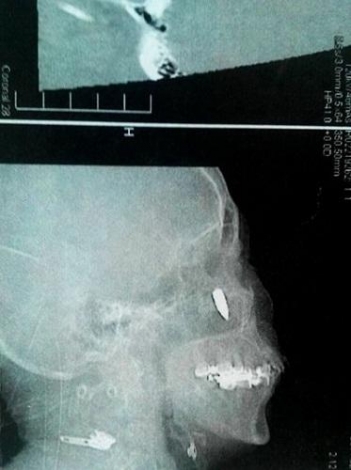

290238019865075423.jpg

醫生從沈陽一位女士頭部取出了一顆子彈,這顆子彈有可能在她頭部待了48年。這次手術解決了她呼吸不暢的問題。